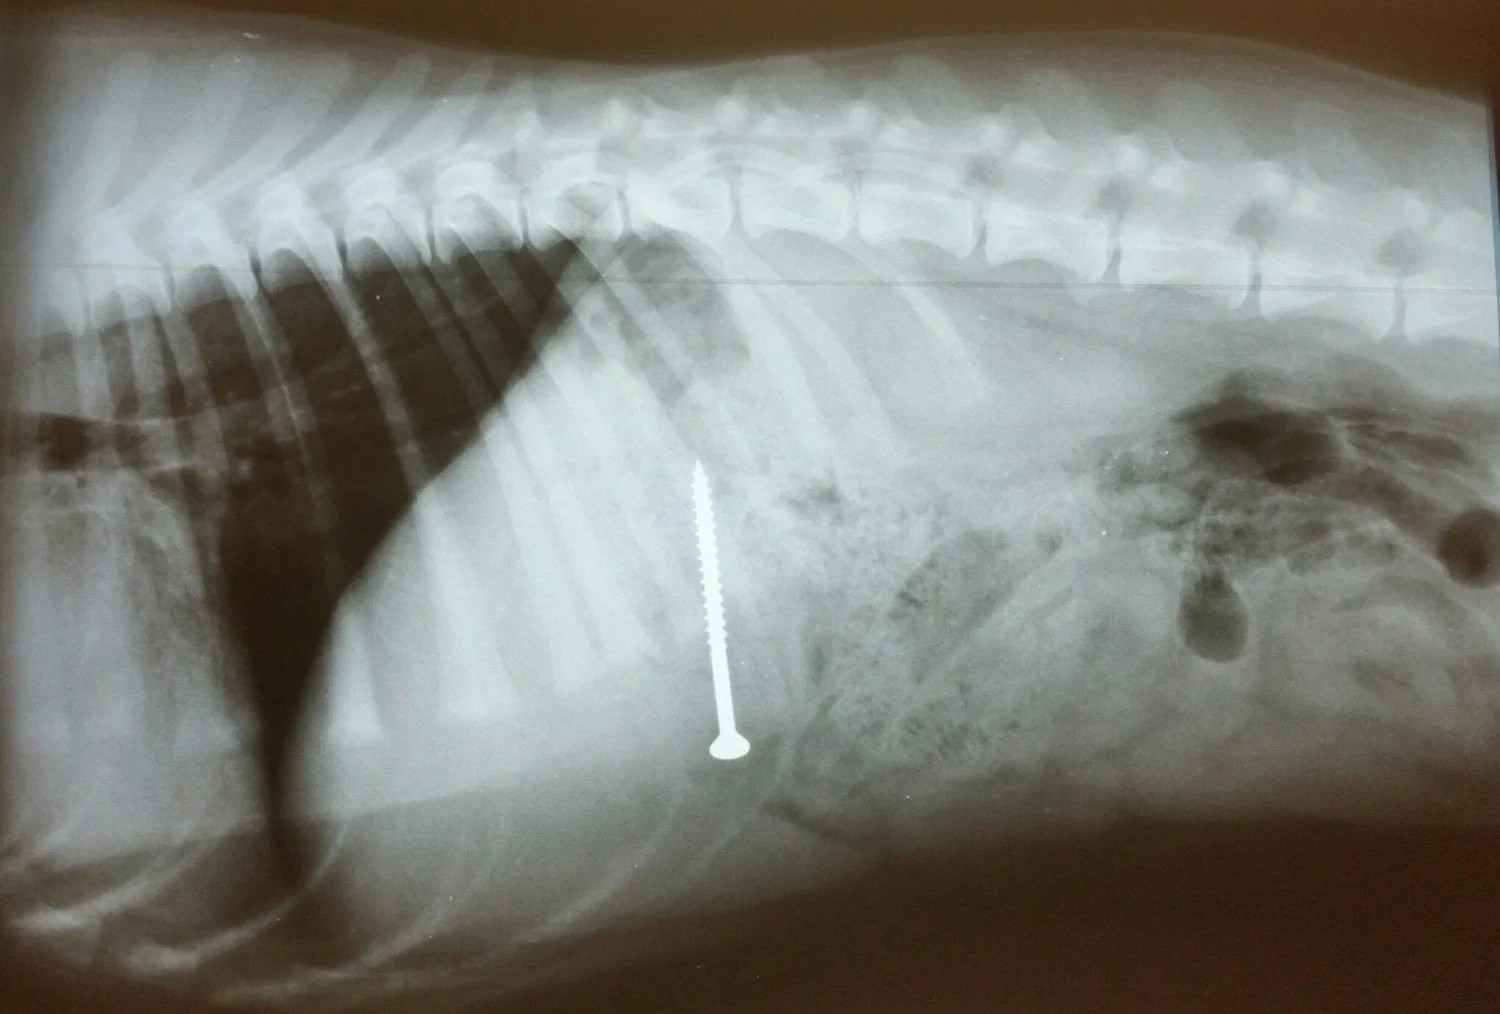

Diagnostic imaging

To locate the foreign body and assess the severity of the situation